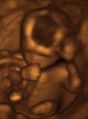

Prenatal development and sonograph images

Prenatal development is divided into two primary biological stages. The first is the embryonic stage, which lasts for about two months. At this point, the fetal stage begins. At the beginning of the foetal stage, the risk of miscarriage decreases sharply, all major structures including hands, feet, head, brain, and other organs are present, and they continue to grow and develop. When the fetal stage commences, a fetus is typically about 30 mm (1.2 inches) in length, and the heart can be seen beating via sonograph; the fetus bends the head, and also makes general movements and startles that involve the whole body. Brain stem activity has been detected as early as 54 days after conception, and the first measurable signs of EEG activity occur in the 12th week. Some fingerprint formation occurs from the beginning of the fetal stage.

One way to observe prenatal development is via ultrasound images. Modern 3D ultrasound images provide greater detail for prenatal diagnosis than the older 2D ultrasound technology. Whilst 3D is popular with parents desiring a prenatal photograph as a keepsake, both 2D and 3D are discouraged by the FDA for non-medical use, but there are no definitive studies linking ultrasound to any adverse medical effects. The following 3D ultrasound images were taken at different stages of pregnancy: